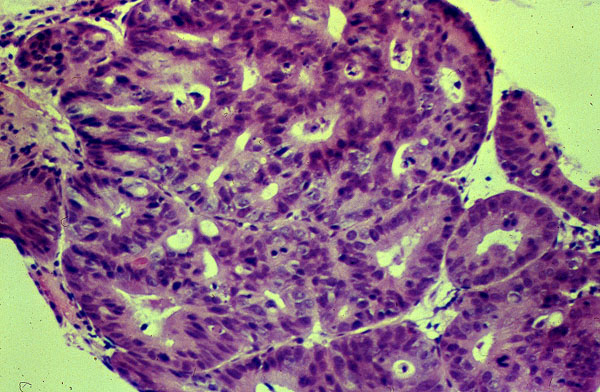

Adenocarcinoma of the esophagus

This tumor which arose in Barrett esophagus in the lower portion of the esophagus is an adenocarcinoma composed of irregular interanastomosing atypical glands.